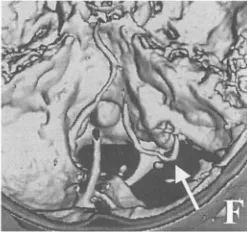

术后三维CT示经小型背外侧颅骨切除并磨除枕骨大孔外侧缘后,肿瘤已全切;右侧椎动脉及寰椎后弓得以保留;箭头示椎动脉水平段后袢。(F)

术后恢复平稳,无并发症。